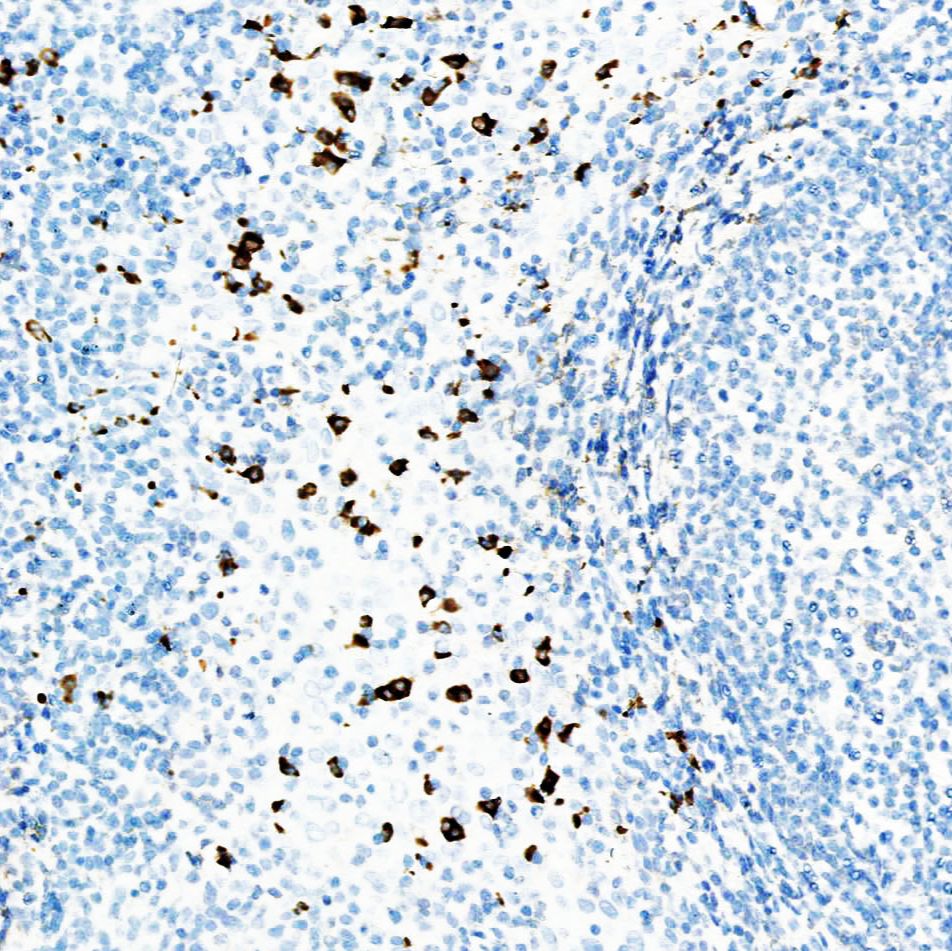

应用:此抗体可以与免疫球蛋白IgA的α链反应。免疫球蛋白A(IgA)在粘膜免疫中起关键作用。它存在于粘膜分泌物如泪液、唾液、初乳、肠液、阴道液、前列腺和呼吸道上皮细胞的分泌物中,并构成了粘膜表面的第一道防线。用于多发性骨髓瘤、淋巴瘤、浆细胞瘤、B细胞来源的霍奇金淋巴瘤和肾小球肾炎的研究。

阳性部位:细胞质

阳性对照:扁桃体